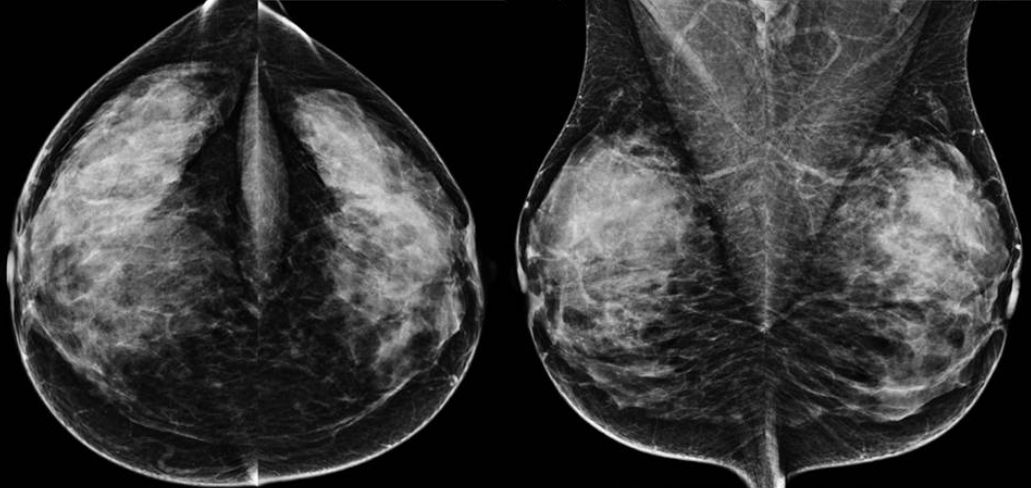

Kontrastmittel-Mammographie: Rekombinationsbild